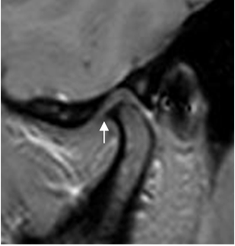

Fig 18 C. Osteoartrosis.

A y B: RM sagital en GE. Cambios degenerativos con irregularidad y erosión en el borde superior del Cóndilo en A, formación de osteofito (Flecha delgada) y quiste subcondral en B. (Flecha gruesa).